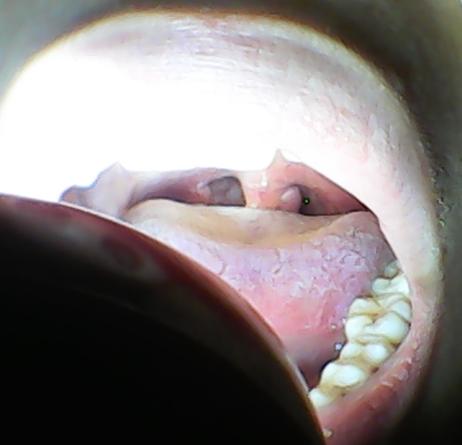

喉咙里面有小泡泡

喉咙里面有小泡泡,喉咙有泡泡

喉咙小舌头有一个球不疼不痒不影响吃东西

喉咙有泡泡

喉咙里面长泡泡图片

喉咙有泡泡图片

小孩喉咙有泡泡图片

喉咙长泡泡图片

喉咙里面图片

喉咙里面图片清晰

喉咙起泡图片

正常喉咙里面的图片

喉咙内壁长泡图片